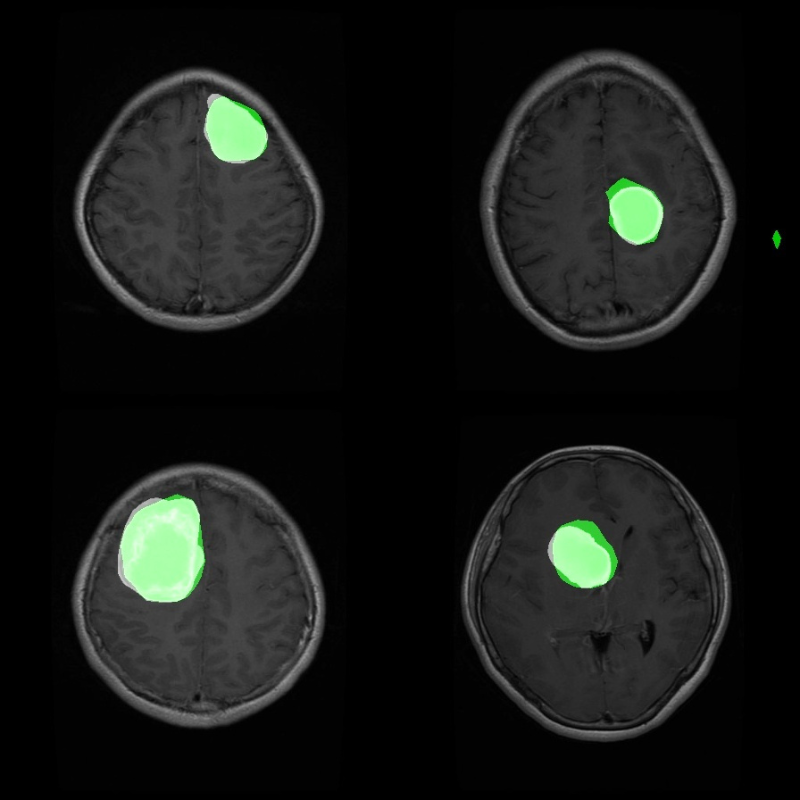

Here are a few results.

Many of us are not medical experts, so we would not be able to determine by sight whether the segmented area is actually a tumor region or not.